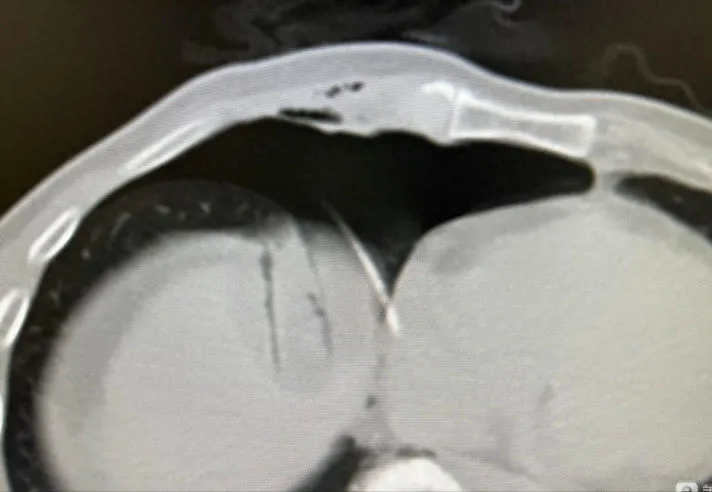

有一位来自福建患者,五年前曾因右肺结节接受了手术切除术。后来左肺又长新的结节,二次手术创伤大,于是患者选择了射波刀治疗。可结节反而长大,并紧靠主动脉,如果消融,容易导致消融不完全,并损伤喉返神经。因此,我在消融前进行人工气胸术,将结节跟主动脉隔开,顺利完成结节的冷冻消融。

在消融前建立人工气胸,通过空气隔离的技术消除消融如邻近纵隔、心脏及大血管的胸部肿瘤以及邻近膈肌的肝顶部肿瘤等盲区,形成足够的安全穿刺空间,以便顺利完成肿瘤的完全消融治疗。同时,在影像技术引导下具有定位精确、图像整体性好及显示穿刺针、进针路径、肿瘤与瘤旁脏器关系的优势,能够为患者提高完全消融率及有效减少并发症发生。

注入500ml气体(最好是CO2),建立人工气胸将肺与膈肌分离开;

冷冻消融清晰显示足够的消融范围;

通过导管抽出气体,肺复张,人工气胸消除;

▲利用肝导向入路seldinger技术,在人工气胸下行膈顶肝癌冷冻消融术。